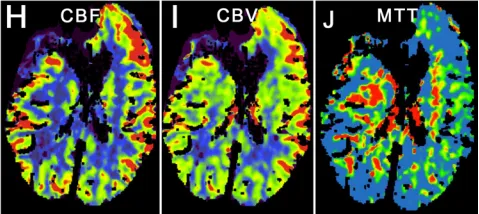

术后脑灌注成像显示一处术前已知的陈旧性脑梗死区域(图1H-J)。患者术后接受随访监测,时长23.9个月。